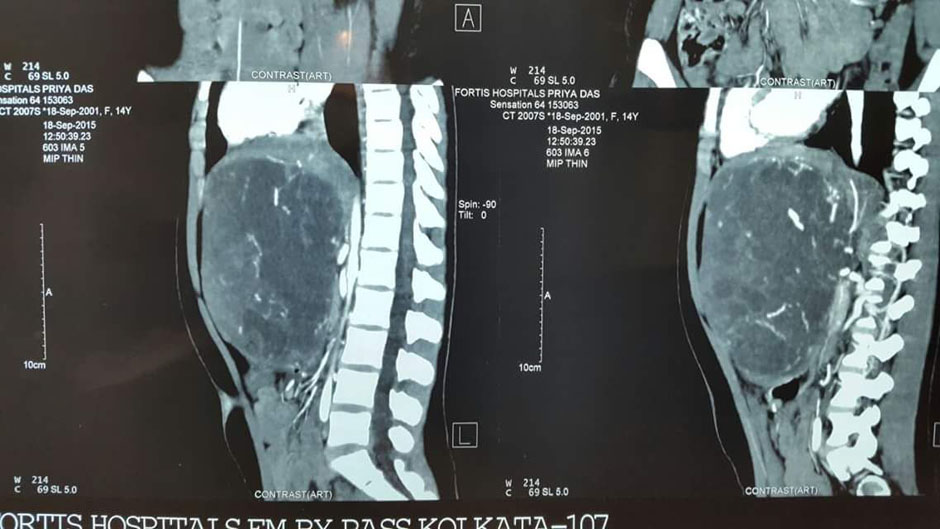

A Young lady who was a small kid...when her mother was operated for a Complex Gastrointestinal condition almost 14 years back by Dr Suddhasattwa Sen suddenly came in with severe blood loss from Gastrointestinal tract with a loss of almost 2 to 3 litres of blood with Shock with fainting . Further stabilisation was done and then extensive investigation revealed not only Piles and GI Ulcers but also SRUS Bleeding ulcers in rectum. A condition called Solitary Rectal Ulcer Syndrome ( a complex and difficult to cure anorectal problem ) . Her hemoglobin dropped to below 7 gm% She finally underwent surgery after 5 days and left home after 2 days post op without any further bleed or problems .